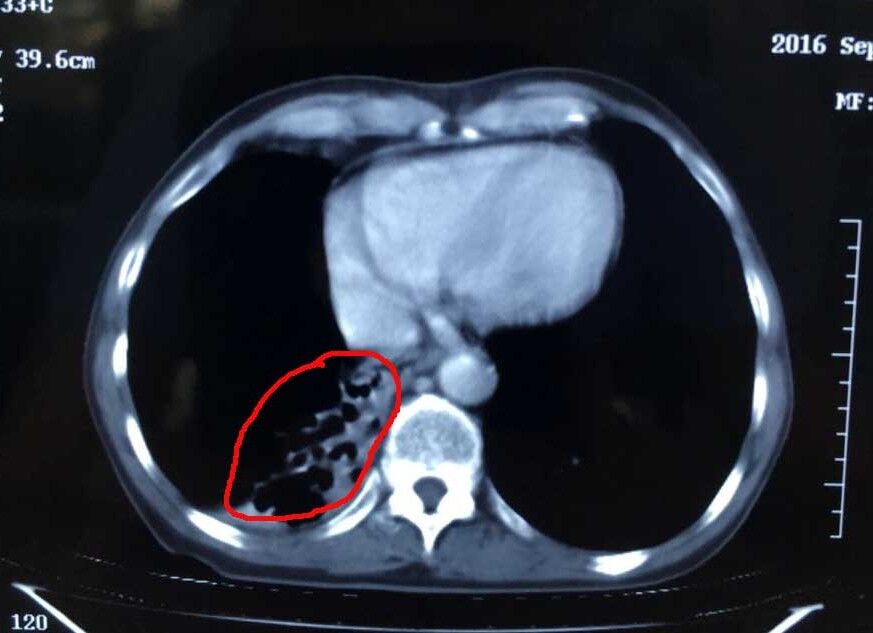

腫瘤治療后